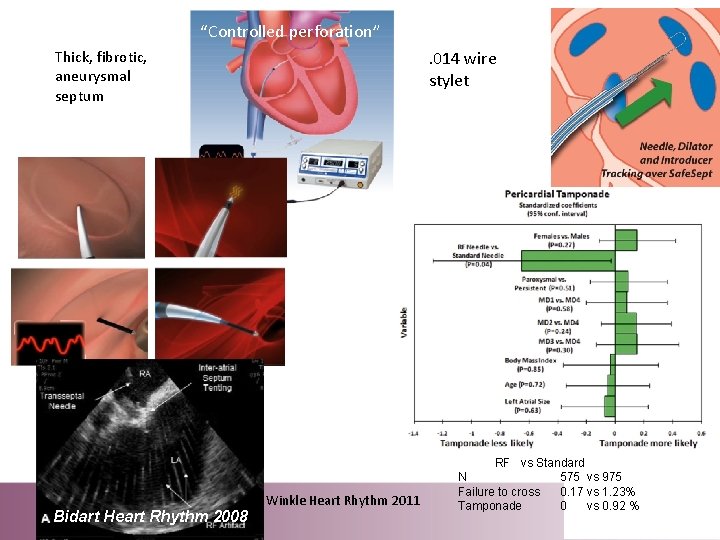

“Controlled perforation”. 014 wire stylet Thick, fibrotic, aneurysmal septum Bidart Heart Rhythm 2008 Winkle Heart Rhythm 2011 RF vs Standard N 575 vs 975 Failure to cross 0. 17 vs 1. 23% Tamponade 0 vs 0. 92 %